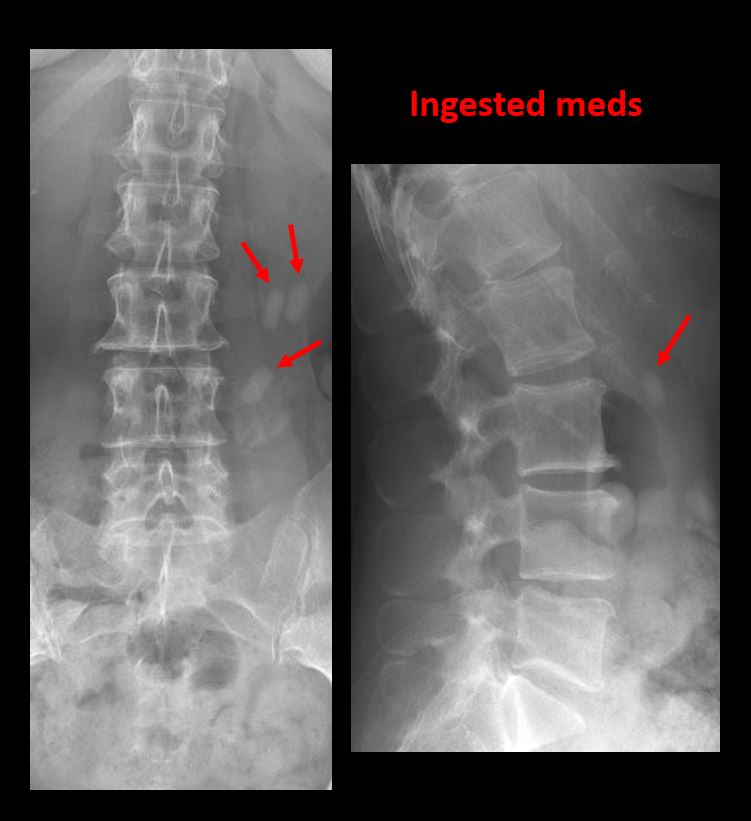

Section 1 Submit Findings CB1239 Findings Technique The thoracolumbar junction and/or the lumbosacral junction is/are not entirely included on the exam. Yes No The exam is over or under penetrated. Yes No The exam is limited by overlying structures, bones or soft tissues, patient positioning, support devices, or motion. Yes No Prevertebral and paravertebral soft tissues The prevertebral or paravertebral soft tissues are abnormal. Yes No Spinal alignment The vertebral bodies are abnormally aligned. Yes No The anterior and posterior vertebral body lines are abnormal or interrupted. Yes No The visualized spinous processes are malaligned or distracted on the AP and/or lateral view(s). Yes No There is reversal or straightening of the normal lordosis or scoliosis of the lumbar spine. Yes No Vertebral bodies, posterior elements and included sacral segments There are more or less than the expected 5 non rib-bearing vertebral bodies. Yes No There is a transitional motion segment at the lumbosacral junction (sacralization of L5 or lumbarization of S1). Yes No There is a fracture or distraction of a vertebral body, transverse or spinous process, or other posterior element. Yes No There is anterior wedging and/or compression of a vertebral body or end plate. Yes No There is an end plate avulsion or other fracture. Yes No There is displacement of a fracture fragment into the soft tissues or spinal canal. Yes No There is lucency or defect of the pars interarticularis from spondylolysis. Yes No There is an abnormality of a pedicle or lamina on the frontal or lateral view. Yes No There is a fracture, erosion, sclerosis, lytic, or blastic lesion of a pedicle or lamina. Yes No There is evidence of a lytic or sclerotic lesion, or disruption of the trabecular pattern of a vertebral body, end plate, or sacrum. Yes No There is a fracture or interruption of the arcuate lines of the sacrum. Yes No There is erosion, sclerosis, narrowing, or other abnormality of a sacral foramen or the SI joints. Yes No There is focal or diffuse abnormal mineralization of the lumbosacral spine. Yes No Disc spaces and facet joints There is distraction or focal widening of a disc space. Yes No There is disc space narrowing with or without erosive or sclerotic changes of the end plates or subchondral bone other than from degenerative change. Yes No There is anterior or posterior spondylolisthesis, subluxation, or rotational abnormality at a disc space. Yes No There is widening, rotational abnormality, or displacement of facets at any motion segment. Yes No There is facet joint narrowing or sclerosis other than from degenerative change. Yes No There is narrowing or encroachment of a neural foramen other than from degenerative change. Yes No There are degenerative changes present that might explain the patient’s symptoms. Yes No Additional soft tissues and bones (lower thorax, abdomen, and pelvis) There is abnormal bowel or bowel gas pattern. Yes No There are gallstones, vascular, renal, pelvic, or other soft tissue calcifications present. Yes No There is free intraperitoneal or retroperitoneal air or other abnormal air in the included chest, abdomen, or pelvis. Yes No The included thoracic spine, ribs, and remainder of the bony pelvis are abnormal. Yes No There is abnormality of the lower chest and/or diaphragm. Yes No There is a foreign body or there are post surgical changes of the bones or soft tissues of the included lower thorax, abdomen, and pelvis. Yes No There is an abnormality or complication of post surgical hardware/device. Yes No N/A There are support lines or tubes in an abnormal position. Yes No Other findings There are other existing conditions that might be contributing to symptoms which can or should be further evaluated non-emergently. Yes No